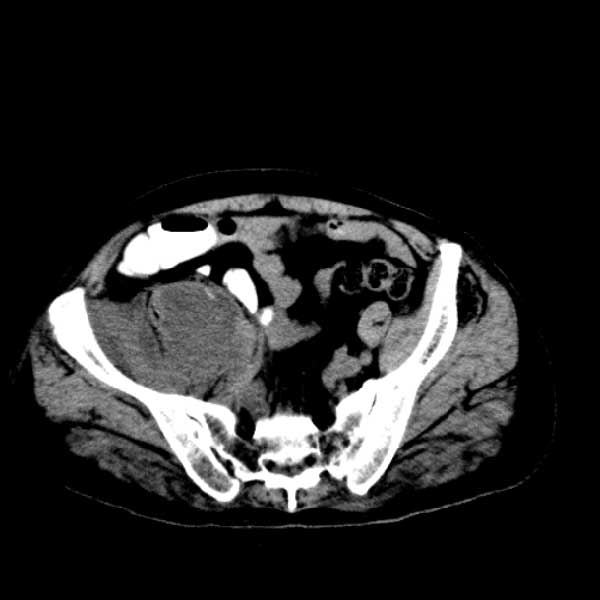

标题: CT13513:男 71 腹部疼痛20余天,近几天高热就诊,骨窗未见异 [打印本页]

标题: CT13513:男 71 腹部疼痛20余天,近几天高热就诊,骨窗未见异

考虑感染性病变可能性大,起源于阑尾?

感染,脓肿形成

考虑为化脓性阑尾炎.脓肿形成.及多肌肉累及.

考虑右侧腰大肌脓肿,向右髂窝、右腹股沟流注。

支持化脓性阑尾炎伴右髂窝脓肿、腰大肌腰方肌脓肿形成。

考虑腹腔及盆腔化脓性炎症,累及右侧髋关节及腹股沟区.

首先考虑化脓性阑尾炎伴腰大肌、腰方肌脓肿,不除外回盲部结核。

回盲部癌待排除。

患者肠镜检查考虑结肠癌,病理证实

患者肠镜检查考虑结肠癌,病理证实。肺部ct可见多发结节,考虑转移